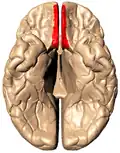

Base del encéfalo. El giro recto está señalado con el número 1. | ||

Superficie basal del del cerebro. La circunvolución recta se muestra en rojo. -